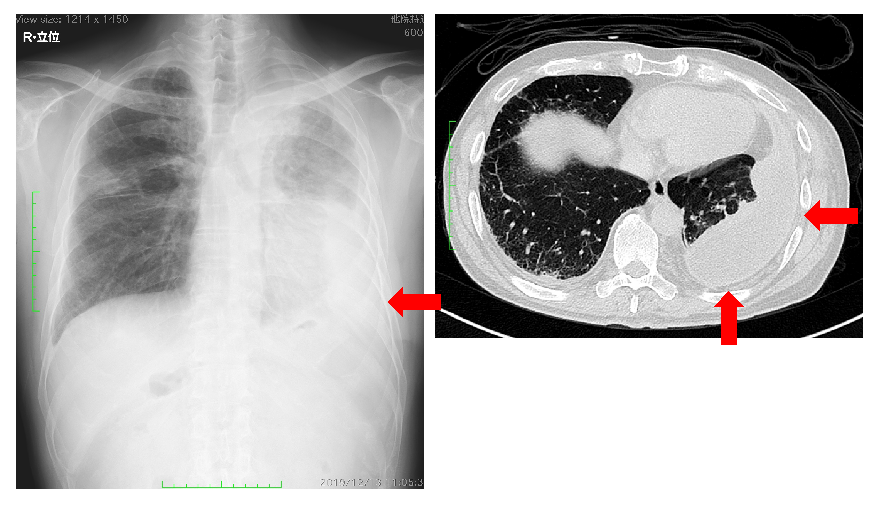

原発性肺癌(右上葉肺癌)の胸部レントゲン写真と胸部CT。矢印は原発性肺癌を示しています。

胸壁へ浸潤した原発性肺癌の胸部レントゲン写真と胸部CT。矢印は原発性肺癌が胸壁へ浸潤しているところを示しています。